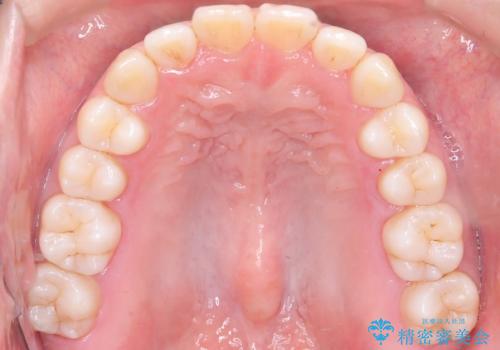

- 「前歯が出ているのが気になる」との主訴で来院されました。診察の結果、上下の前歯が前方に突出し、口元がやや目立つ印象でした。また、歯列の中心線(正中)も上下でずれており、かみ合わせのバランスにも問題がありました。

治療はまず精密スキャンとシミュレーションを行い、TADを使用して奥歯を遠心移動(後方へスライド)させる設計を組み込みました。マウスピースは計画に沿って順次交換し、TADと連結しながらコントロールすることで、歯列全体を無理なく整えていきました。

前歯の傾きが改善され、横顔の印象が大きく変化。上下の正中も一致し、かみ合わせのバランス(臼歯関係)も整いました。目立たず快適に治療ができた点にもご満足いただき、「人に気づかれずにここまで変化できるとは思わなかった」とのお声をいただいています。治療後はリテーナーを用いて、仕上がりをしっかり保っています。